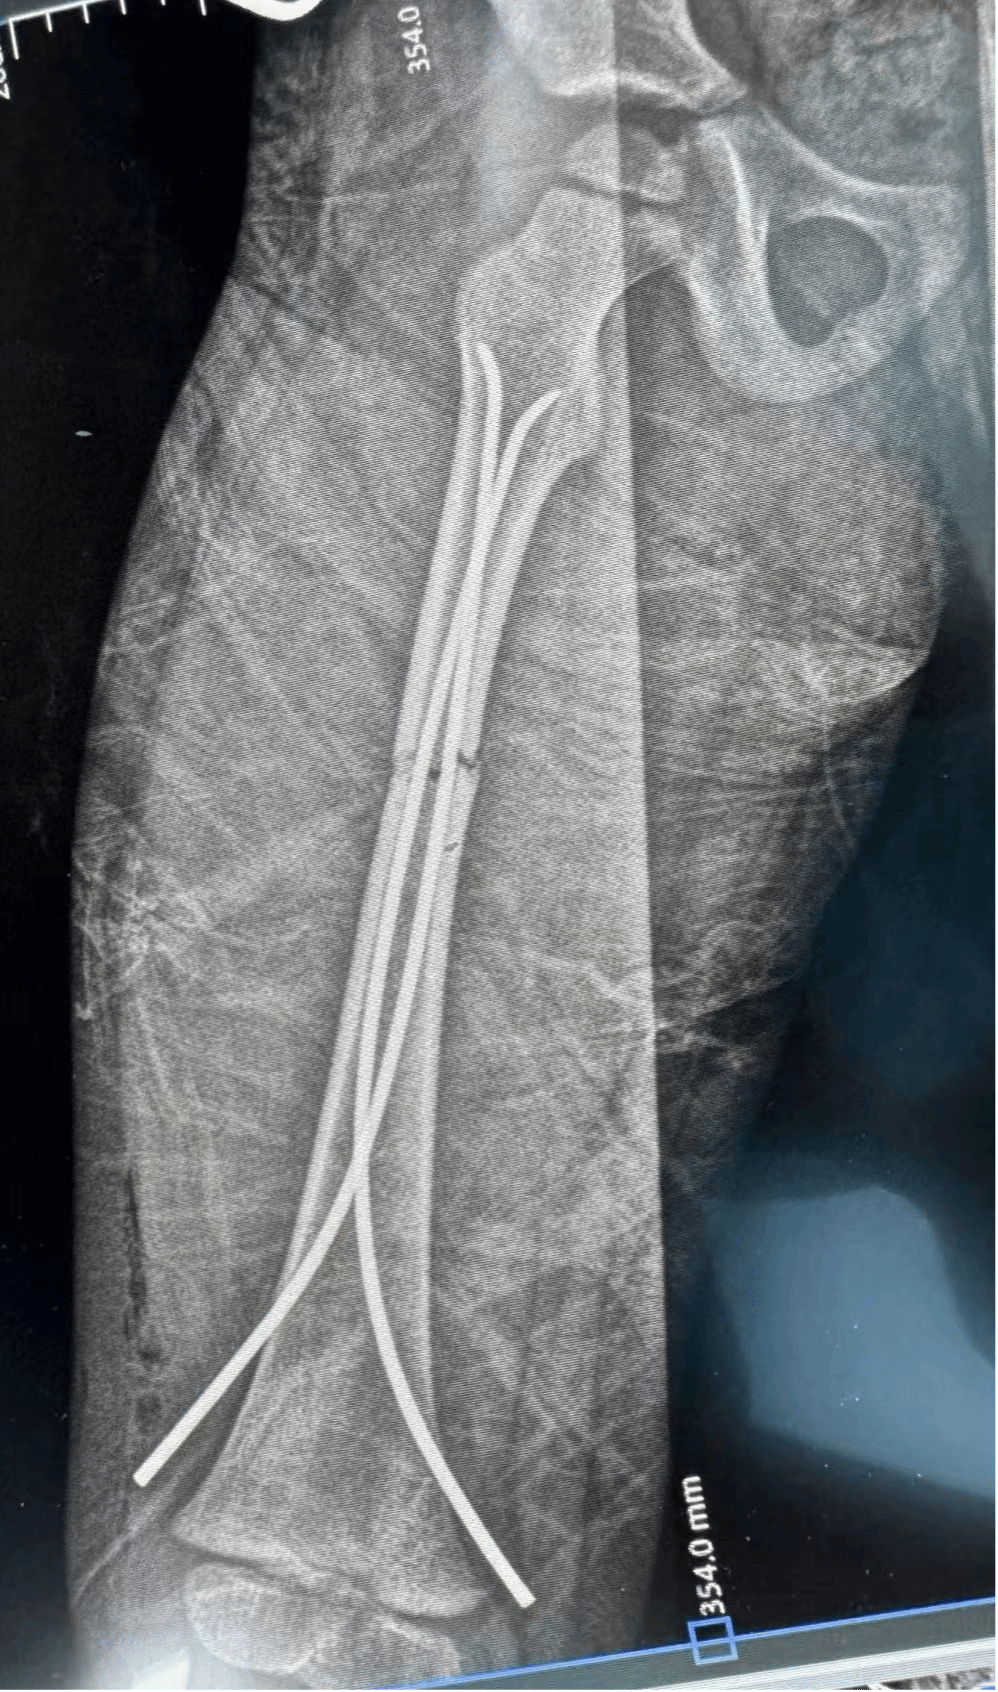

股骨干骨折闭合复位弹性髓内钉内固定术

4.对于5~8岁患者且患者难以配合牵引治疗者,可考虑弹性髓内钉固定;

6.较大儿童骨折错位严重,牵引复位不满意,短缩超过两个厘米,可考虑行手术复位或者进行闭合的复位,固定治疗。有的因为骨折不稳定,需要切开内固定,现在广为临床应用的是钢板内固定和髓内钉固定;